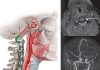

Havayolu

Travmalı hastaların değerlendirilmesinde en öncelikli sistem hava yoludur. Erken dönemde en önemli ölüm nedeni hava yolu obstrüksiyonuna veya trakeobronşiyal yaralanmaya bağlı beyin ve diğer hayati organlara oksijenize kanın ulaşamasıdır. Bir çok ölüm;

- Tıkalı hava yolu tanımada veya yetersiz solunumu tanımada gecikme

- Gerektiği halde hava yolunu açmada ve solunumu desteklemekte gecikme

- Teknik zorluklar (özefagus/sağ ana bronş)

- Gastrik içeriğin aspirasyonu

bağlı gerçekleşmektedir.

Hava yolunun açık olduğundan emin olunmadan diğer sistemlerin muayenesine geçilmemelidir. Hırıltılı solunum, siyanöz ve yardımcı solunum kaslarının kullanılması hava yolu obstrüksiyonuna işaret eder. İlk değerlendirme sırasında, ağız ve orofarenkste yabancı cisim (pıhtı, kan, kusmuk, cam parçacıkları, diş protezi vb.) varlığı araştırılmalı ve hava yolu obstrüksiyonu yapabilecek yüz, mandibula, larenks ve trakea fraktürlerinin olup olmadığı kontrol edilmelidir. Şuuru kapalı hastalarda dil öne çekilerek airway (hava yolu) adı verilen, dilin arkaya kaçıp solunum yolunu tıkamasını engelleyecek plastik bir aparey yerleştirmelidir. Apne varlığı, alt solunum yollarına aspirasyon riski, basit yöntemlerle hava yolu açıklığının sağlanamaması ve hava yolunun tehdit altında olması (inhalasyon yanıkları, ağır yüz travmaları, sürekli konvülziyon vb.) gibi koşullarda kalıcı hava yolu gerekir. Bu amaçla; entübasyon, veya cerrahi hava yolu ( iğne krikotiroidotomisi, cerrahi krikotiroidotomi ve trakeotomi) endikasyonlarına göre seçilerek uygulanır.

Hava yolunun açık tutulması sırasında servikal vertebra travması olasılığı da akıldan çıkarılmamalıdır. Bu amaçla boynun bilinçsizce hareket ettirilmemesine ve bu olasılık ortadan kalkana kadar immobilize edilmesine özen gösterilmelidir. İdeal olanı sert tipte “Philadelphia collar” olarak adlandırılan boyunlukları kullanmaktır. Servikal immobilizasyon için tıklayınız.